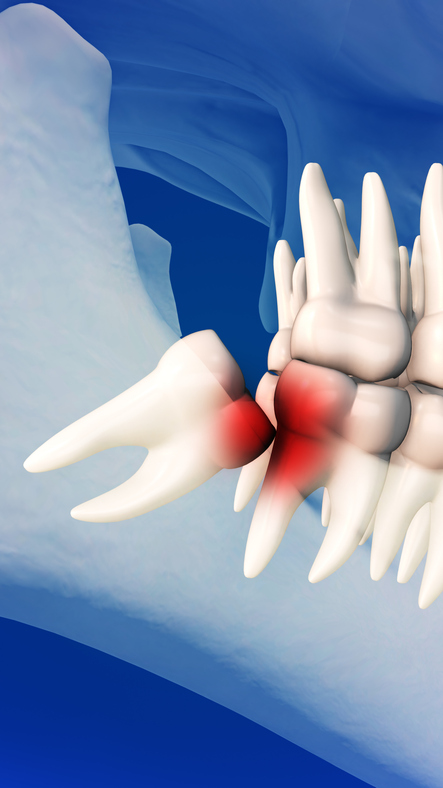

Wisdom teeth are the last teeth to come in, and many people’s mouths aren’t big enough to accommodate them. When a person’s wisdom teeth try to erupt in a crowded environment, you can experience issues ranging from impaction (stuck under the gum), to partial eruption, to eruption at an angle that puts pressure on nearby teeth and creates a difficult area to keep clean. Over time, this can even lead to cavities on the 2nd molars, which if the damage becomes severe enough, could require the 2nd molars to be extracted as well.

- Your wisdom teeth are impacted (stuck under your gum) or only partially erupted.

- Your wisdom teeth are coming in at an angle, putting pressure on molars in front of them.

- You’re experiencing a condition called pericoronitis where the gum tissue surrounding the wisdom tooth becomes inflamed. This often happens when excess gum tissue is irritated by chewing, food getting trapped beneath the gum, or plaque building up in the area and calcifying.